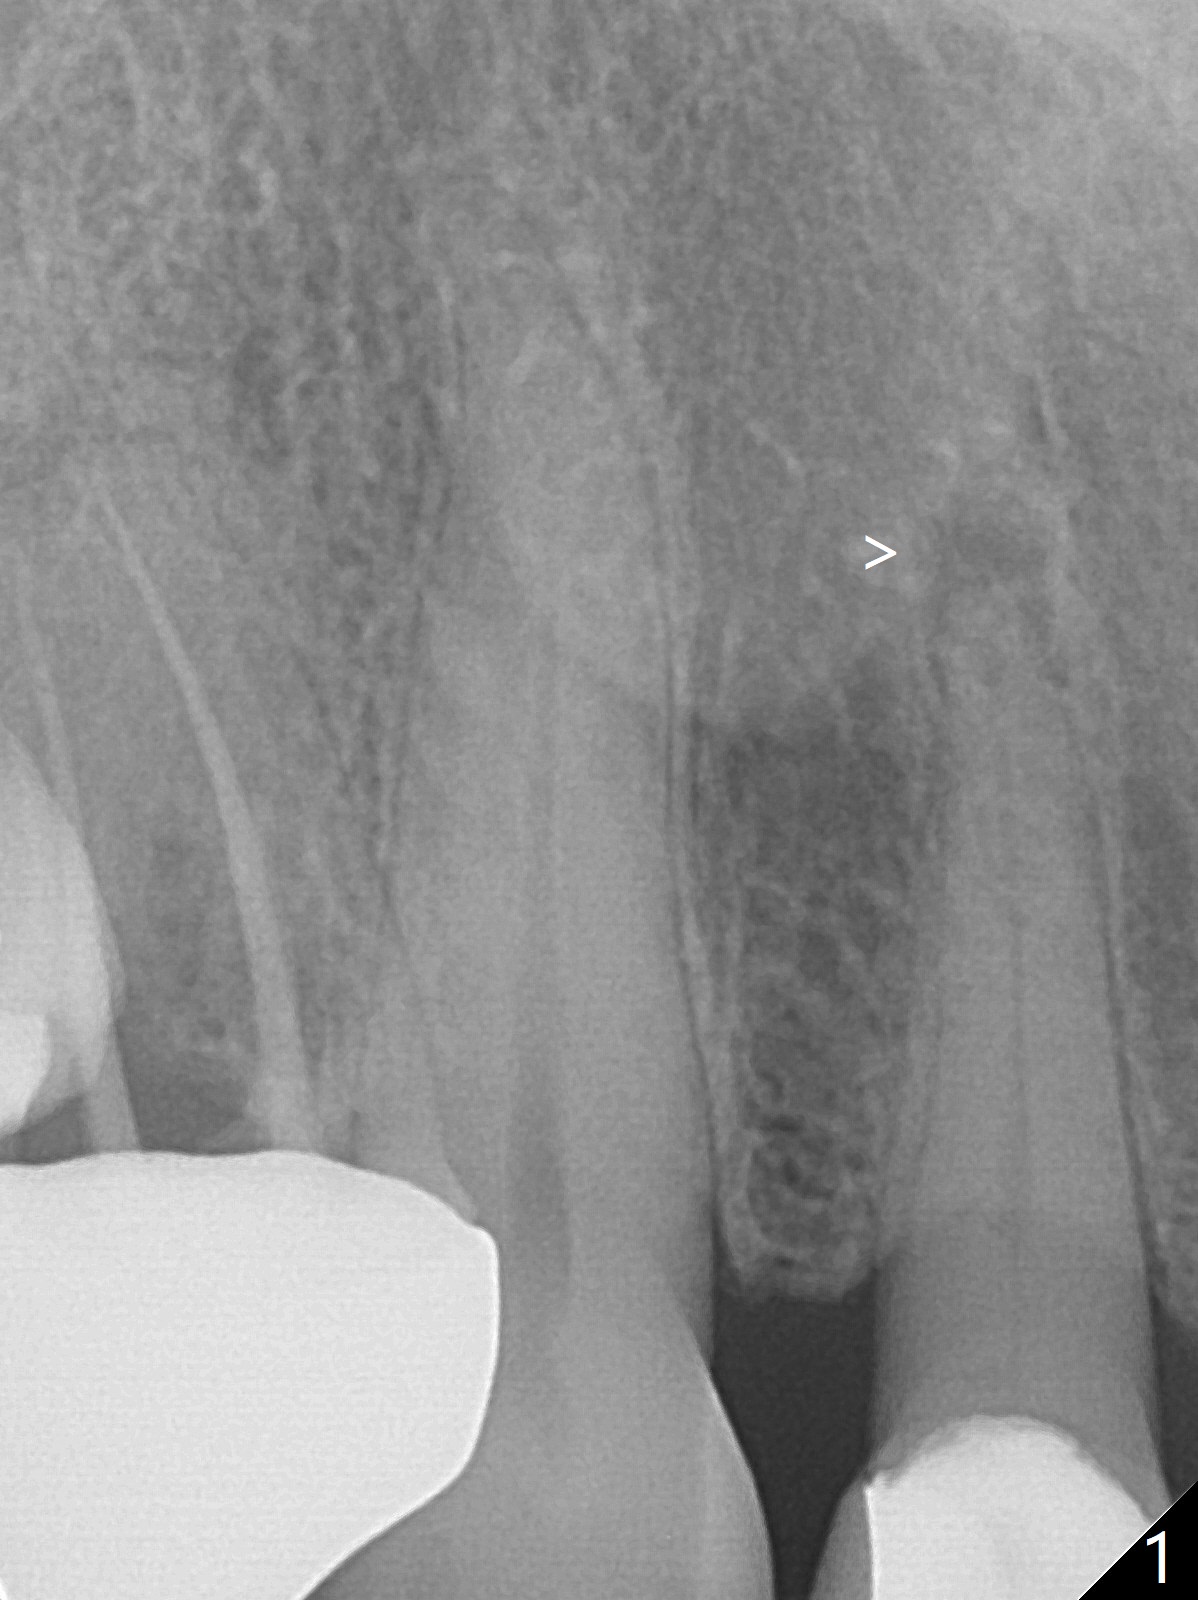

A 63-year-old woman has felt the tooth #7 with a crown and PARL loose for the last 4 months (Fig.1 >).  The crown finally fractures equigingival.  It appears that the best option is extraction and implant (Fig.2).  A 13 mm long implant seems to be short.  A 15 or 16 mm long bone-level or 17 or 20 mm tissue-level one is more appropriate.  To prevent buccal crest and plate loss, socket shield will be performed.  Since the tooth is necrotic, make sure to remove the pulp.